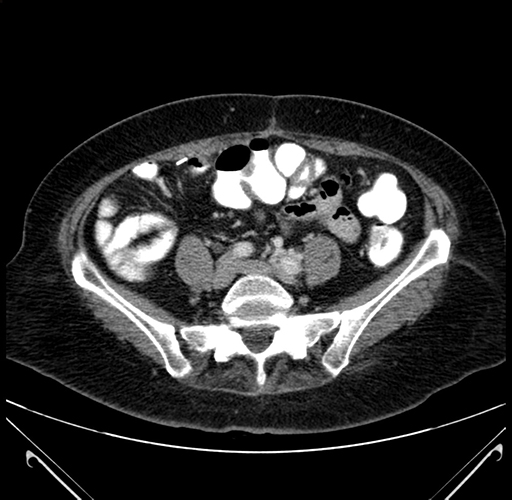

Pre-Chemo: Coronal Venous

Coronal Venous